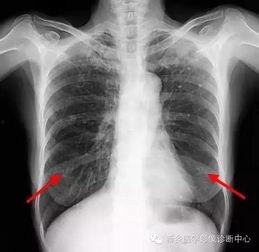

胸片检查是诊断肺部疾病的重要手段。通过观察肺部影像,医生可以初步判断患者是否患有肺炎、肺结核、肺癌等疾病。

胸片检查还可以用于诊断心脏疾病,如心包积液、心脏增大等。

对于胸部外伤患者,胸片检查可以迅速判断伤情,为后续治疗提供依据。